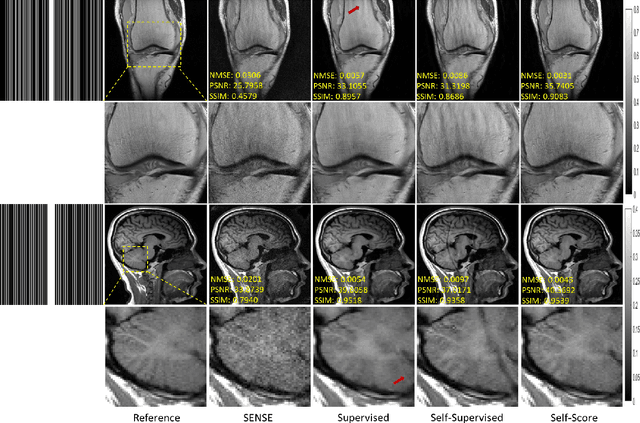

Abstract:Recently, score-based diffusion models have shown satisfactory performance in MRI reconstruction. Most of these methods require a large amount of fully sampled MRI data as a training set, which, sometimes, is difficult to acquire in practice. This paper proposes a fully-sampled-data-free score-based diffusion model for MRI reconstruction, which learns the fully sampled MR image prior in a self-supervised manner on undersampled data. Specifically, we first infer the fully sampled MR image distribution from the undersampled data by Bayesian deep learning, then perturb the data distribution and approximate their probability density gradient by training a score function. Leveraging the learned score function as a prior, we can reconstruct the MR image by performing conditioned Langevin Markov chain Monte Carlo (MCMC) sampling. Experiments on the public dataset show that the proposed method outperforms existing self-supervised MRI reconstruction methods and achieves comparable performances with the conventional (fully sampled data trained) score-based diffusion methods.